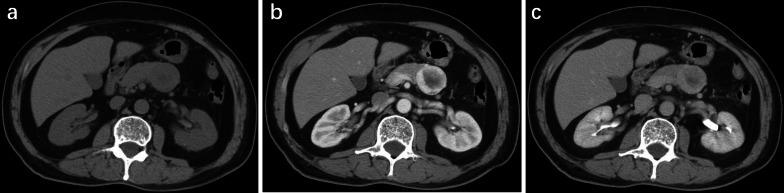

Patients with pancreatic MiNEN more frequently presented with large size and heterogeneous and cystic components compared with PDAC (p < 0.031) and ill-defined irregular margins, progressive enhancement, and adjacent organ involvement compared with NET (p < 0.036). However, vascular invasion was less commonly seen in MiNEN than PDAC (p = 0.010). Moderate enhancement was observed more frequently in MiNEN than in PDAC or NET (p < 0.001). Multivariate logistic analyses demonstrated that moderate enhancement and ill-defined irregular margin were the most valuable features for the prediction of pancreatic MiNEN (p ≤ 0.044). The combination of the two features resulted in a specificity of 93.8%, sensitivity of 83.3%, and accuracy of 91.7%.

We have mainly described the radiological findings of pancreatic MiNEN with ill-defined irregular margin and moderate enhancement compared with PDAC and NET. The combination of imaging features could improve diagnostic efficiency and help in the selection of the correct treatment method.